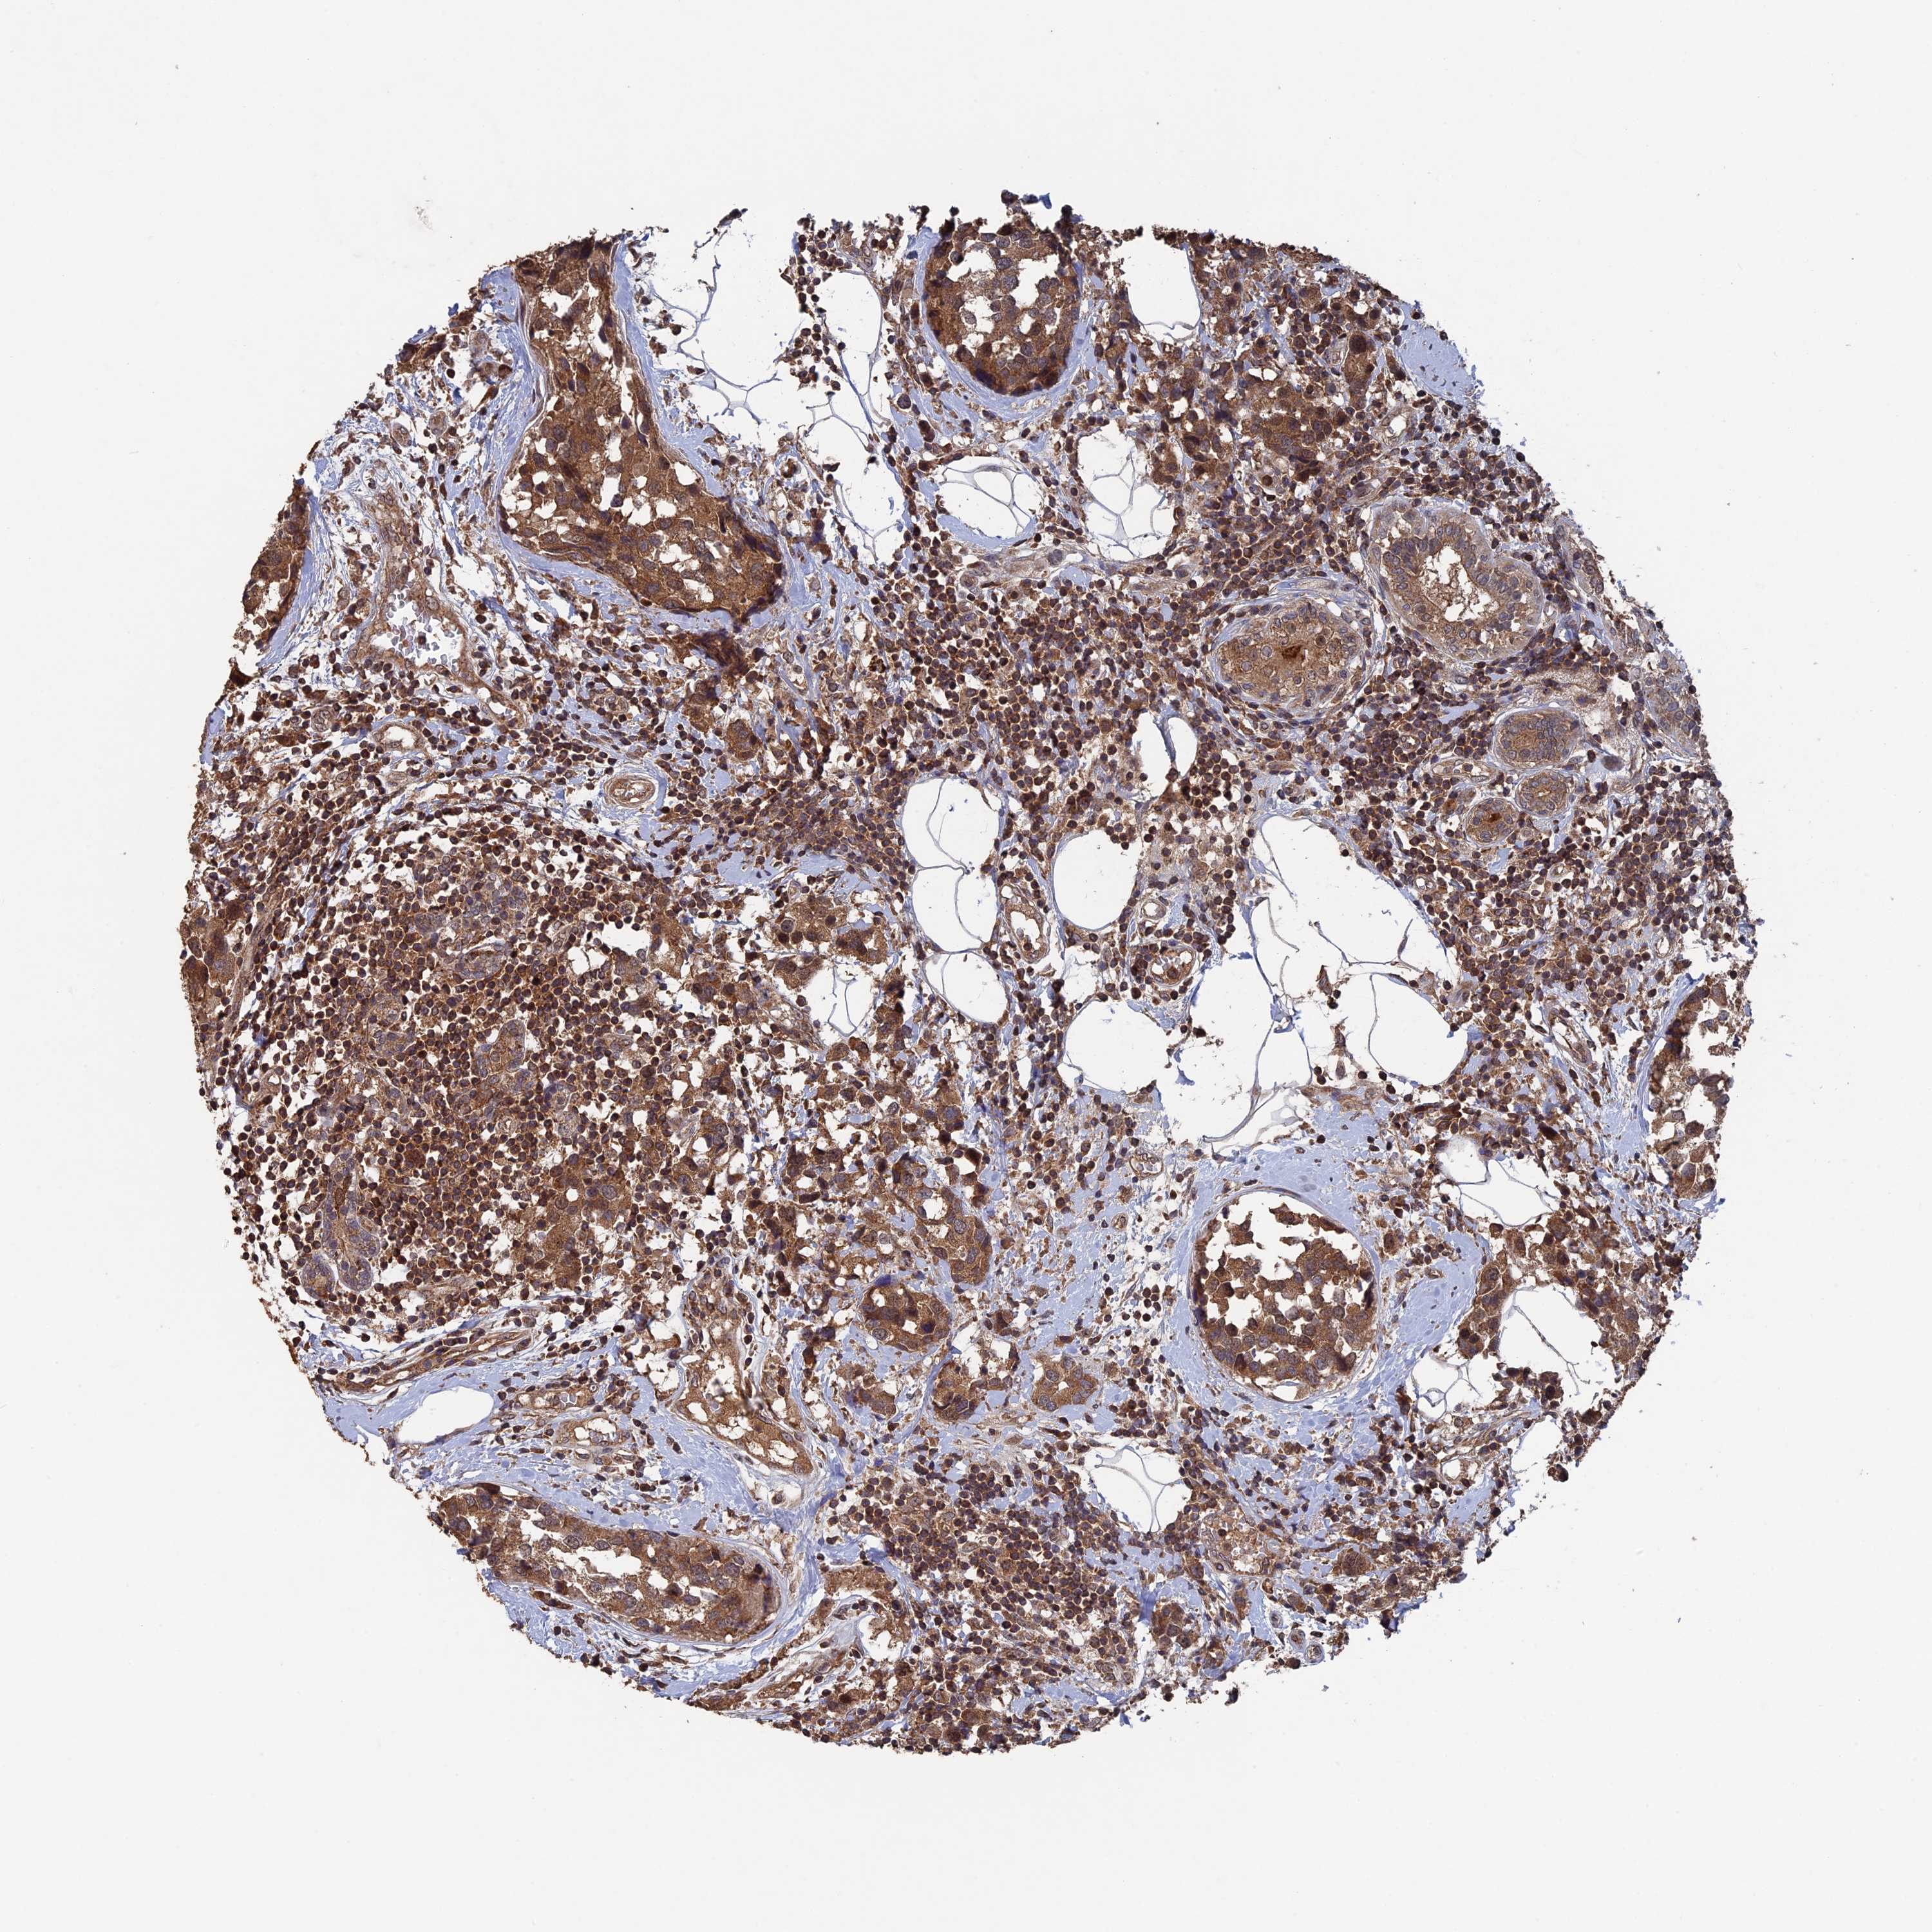

BRCA TCGA BRCA VALIDATION PROTEIN EXPRESSION